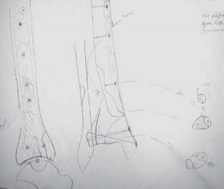

FIG 5 • Preoperative plan for tibial plafond fracture reconstruction.

28. Preoperative planning allows the surgeon to work through the case “on paper” while minimizing risk and often preventing unnecessary delays during the surgery.

29.

A preoperative tracing ( FIG 5) can help with instrumenta- tion needs, surgical approaches, anticipated reduction methods, and implant strategies (selection and placement).